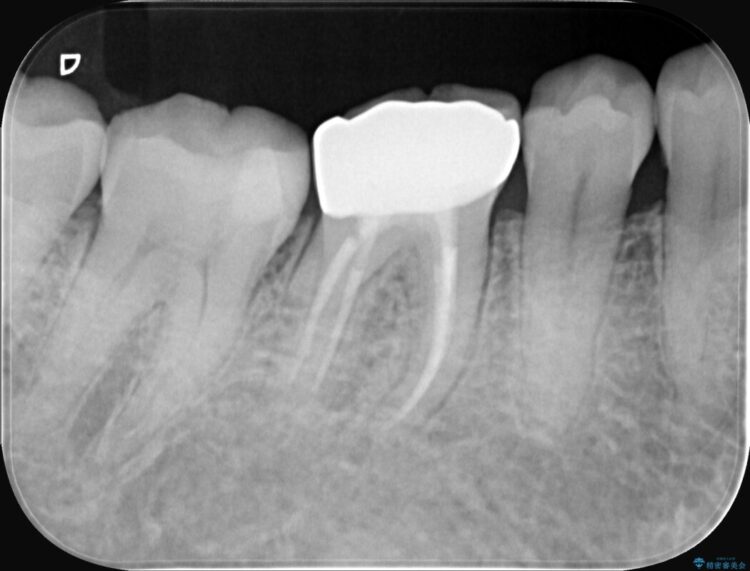

精密検査の結果、根の先に大きな病変が認められますが、根管内が狭窄し湾曲しているため、非常に難易度の高いケースです。

通常の治療器具では奥まで届かず、そのままでは再発や抜歯になるリスクが高いため、マイクロスコープを使用して根の奥まで精密に清掃・殺菌し、歯を残すための治療計画を立てました。

治療では、マイクロスコープで根の中を大きく拡大し、非常に細くなっていた神経の通り道を慎重に見つけ出しました。

次に、根のカーブに沿ってしなやかに曲がるニッケルチタンファイルを使い、根の先まで徹底的に洗浄・殺菌を行いました。汚れを完全に取り除いた後、隙間なくお薬を詰めて密閉しています。

術後の経過は非常に良く、あんなに大きかった膿の袋は消え、健康な骨が再生しているのが確認できました。痛みや腫れも消えて抜歯を免れ、現在は被せ物を入れてしっかりお食事を楽しんでいただけるようになっています。